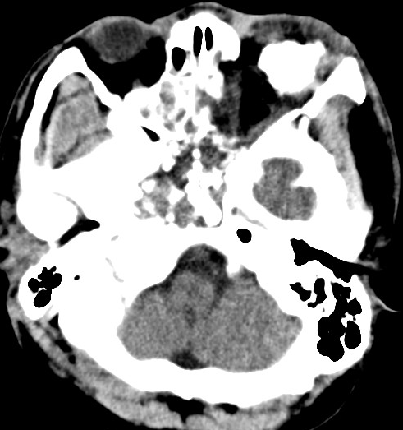

2014-9-29 CT